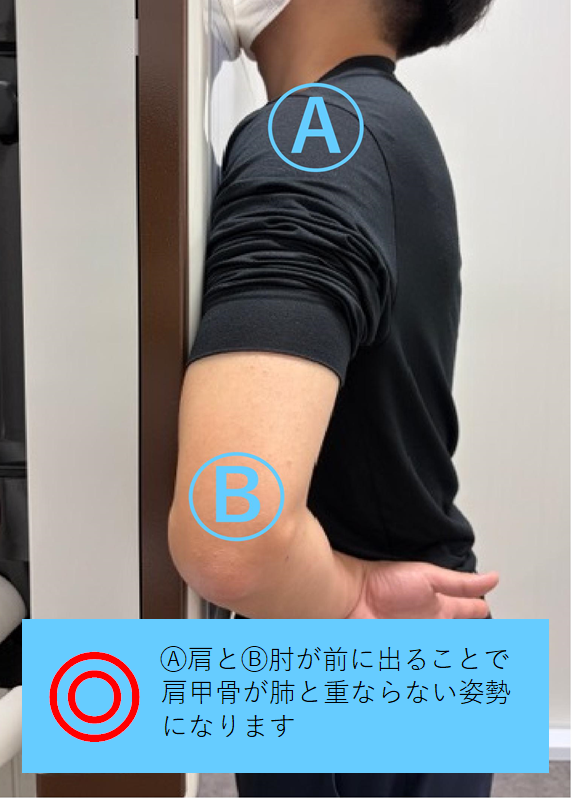

ポイント② 肩と肘をできるだけ前(装置側)へ

Ⓐ肩はできる限り装置に近づける

Ⓑ手のひらを外側に向けることで、

肩甲骨が肺と重ならない姿勢になります